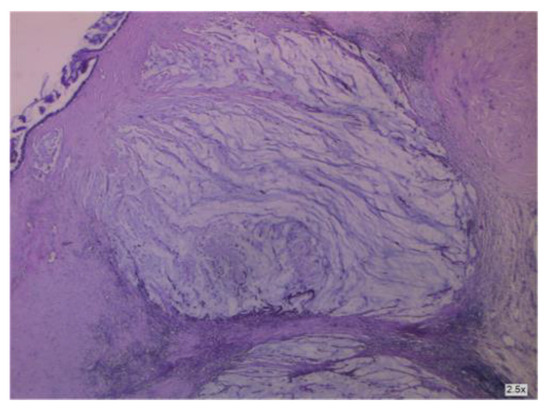

3.2.2. Clinical and Pathology Findings

3.1.6. A Mucinous Borderline Tumor Developing inside an Ovarian Teratoma

- Ryu, J.M.; Jeong, Y.Y.; Choi, Y.S.; Lee, S.J. A rare case of pseudomyxoma peritonei caused by borderline mucinous tumor arising from primary mature cystic ovarian teratoma. Eur. J. Gynaecol. Oncol. 2022, 1, 4. [Google Scholar] [CrossRef]